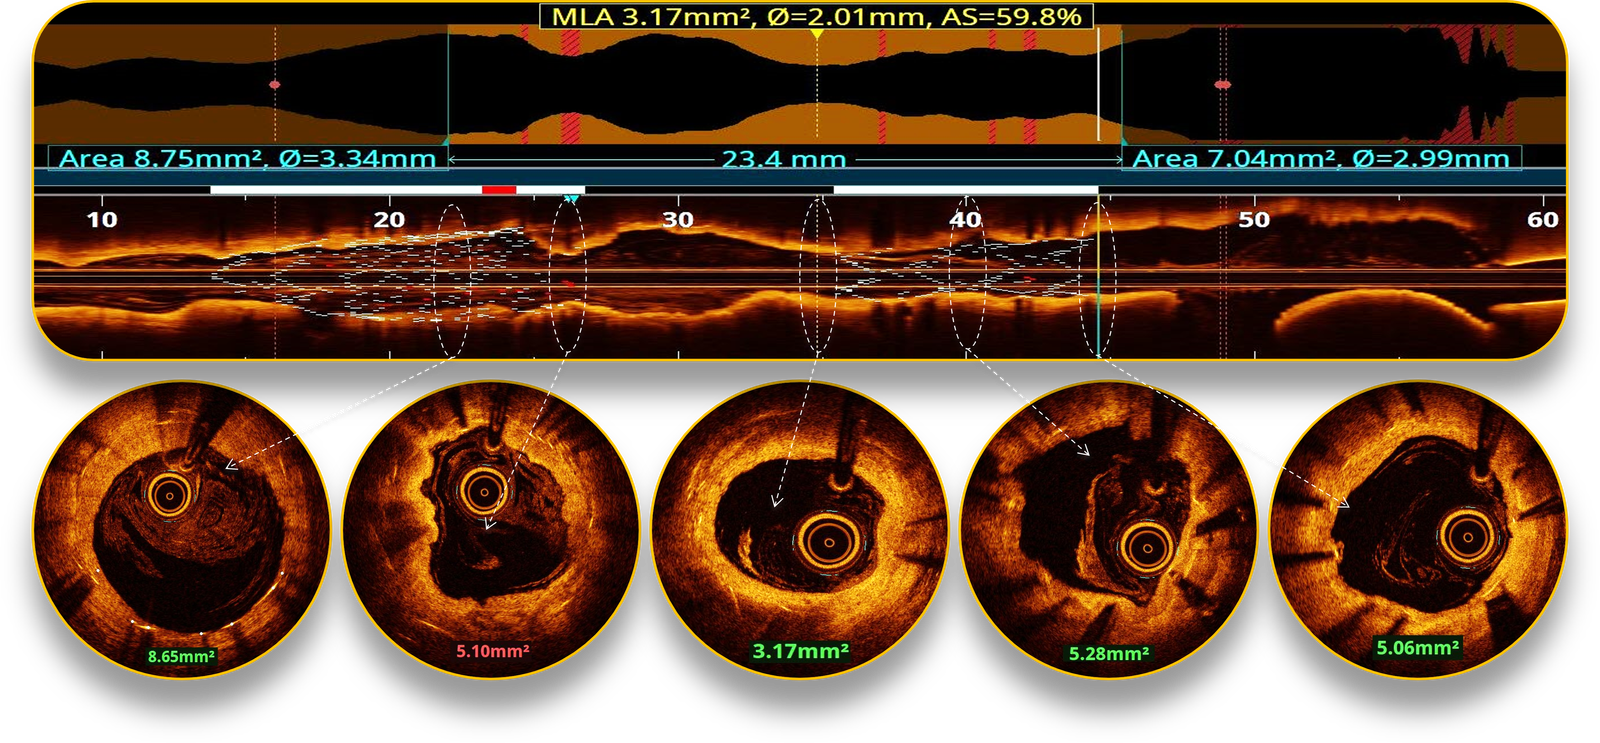

LAD follow-up OCT-run ISR Ca++ score analysis.